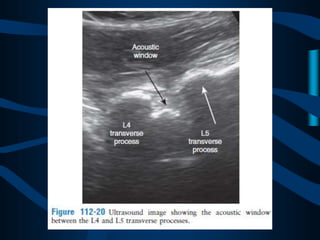

PARAESPINOSO

MEDIAL